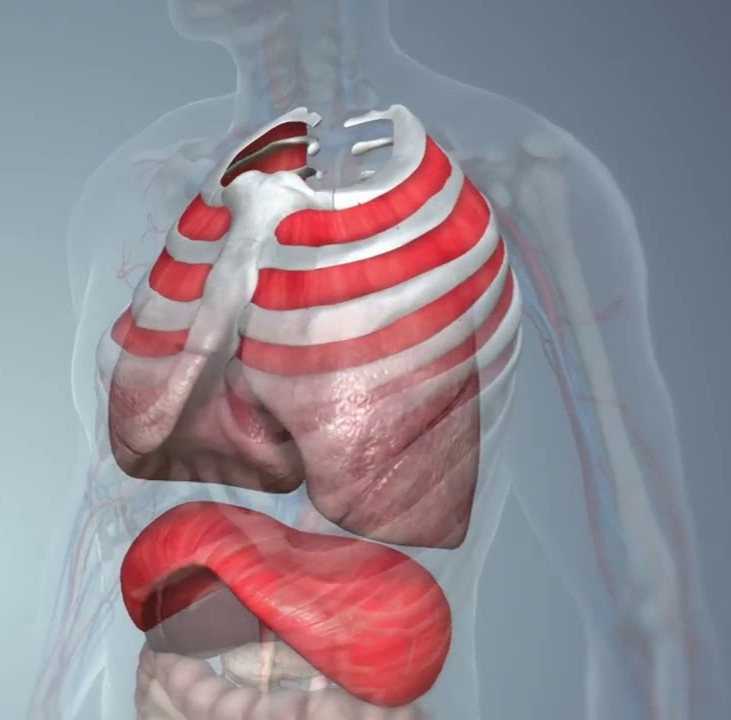

폐암 초기증상 두번째는 가슴통증입니다. 폐암 환자의 약 3분의 1이 고통을 느낀다고 합니다. 폐 제일자리에 폐암이 발생하다 보면 암세포가 흉막과 흉벽을 침범해 찌르는 듯한 통증을 유발합니다. 암이 더 진행되면 진행될 수록 통증이 더 계속됩니다. 갈비뼈까지 퍼지는 통증의 경우로 볼 수 있습니다.위치에 따라 요통으로도 진행이 되기도 합니다. 흉통이 생기는 곳은 폐의 제일자리에 폐암이 일어날 때 나타나고 흉막에 암이 인접해 위치하다 보면 바늘로 콕콕 찌르는 듯한 흉통을 느끼게 되며 폐암이 갈비뼈나 다른 부위로도 전이될 해당에도 흉통이 발생하고 요통으로도 발전할 수 있습니다.